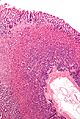

Microscopic

Features:

- Signet ring cells resemble signet rings.

- They contain a large amount of mucin, which pushes the nucleus to the cell periphery.

- The pool of mucin in a signet ring cell mimics the appearance of the finger hole.

- The nucleus mimics the appearance of the face of the ring in profile.

- Signet ring cells are typically 2-3x the size of a lymphocyte.

- Smaller than the typical adipocyte.

- Often have a crescent-shaped or ovoid nucleus.

- Capillaries sectioned on their lumen have endothelial cells - the nuclei of these are more spindled.

Note:

- SRCs are usually close to friend, i.e. they are adjacent to another SRC.

- This helps differentiate SRCs from capillaries sectioned on their lumen.

- The mucin is often clear on H&E... but maybe eosinophilic.